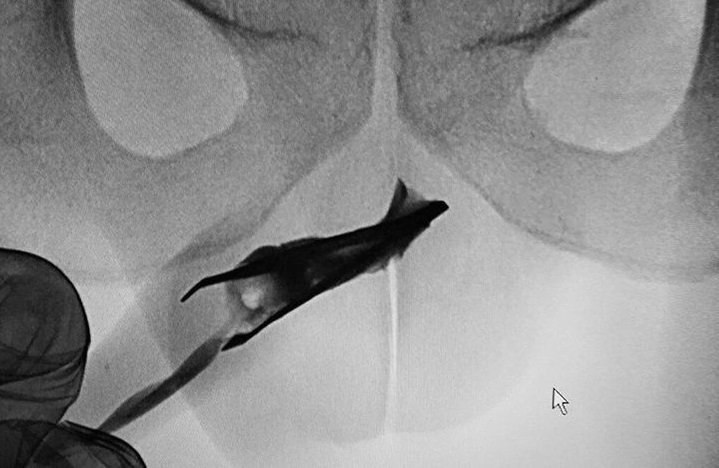

یک موچین ۸ سانتیمتری، چهار سال در مجرای ادرار یک مرد جوان ۲۲ ساله در عربستان سعودی گیر کرده بود. این جوان ادعا کرد که هیچ مشکلی، مثل عفونت و تب نداشت و راحت ادرار می کرد. هافینگتون پست نوشت در موارد خیلی نادر، برخی مردها برای ارضای جنسی یک شی خارجی وارد مجرای ادرار خود می کنند!

به نوشته دیلی‌میل یک جور #فتیش_جنسی در #خودارضایی است به اسم #sounding. در این حد رایج هست که ابزارهای خاص (و لابد ایمن!) خودش رو داره در بازار. دو عکس آخر بالا از فروشگاه آمازون: amazon